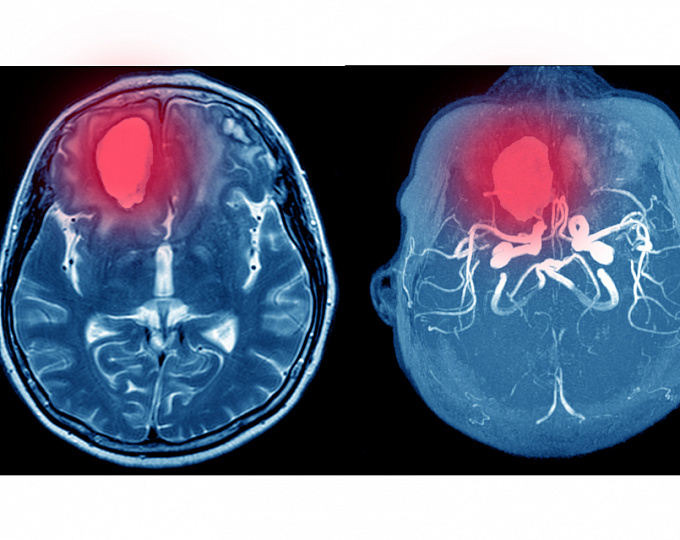

Открытое овальное окно и криптогенный инсульт у пожилых пациентов

Известно, что наличие открытого овального окна рассматривается как причинный фактор при криптогенном инсульте. Для пациентов моложе 60 лет, ранее перенесших криптогенный инсульт, несколько рандомизированных исследований, а также их мета-анализ продемонстрировали снижение риска повторного инсульта при выполнении закрытия открытого овального окна.

Однако неопределенной остается тактика для пациентов, имеющих открытое овальное окно, возраст которых на момент первого криптогенного инсульта составляет 60 лет и больше. В связи с чем целью обсуждающегося исследования стала оценка риска повторного инсульта у пациентов, перенесших криптогенный инсульт и имеющих открытое овальное окно в зависимости от возраста.